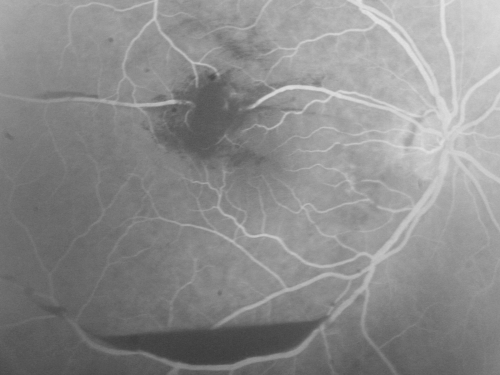

Retinal Arterial Macroaneurysm - Increased Swelling after Laser

March 21, 2011.  This pleasant 66-year-old woman had laser to retinal arterial microaneurysm in the right eye January 12th.  Her vision was getting better, but now it is worse the last few days.  She is at home taking care of her demented mother and she and her sister lift her mother a fare amount of the time.  I also checked her blood pressure, which was 120/65.  VISUAL ACUITY:  OD 20/200